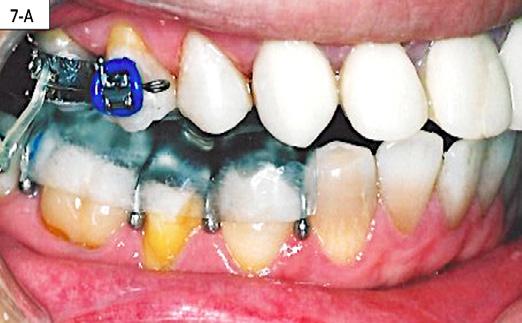

After the patient became accustomed wearing the splint, the acrylic was cut off distally to #46(30) and #36(19). A band was cemented on #17(2), #16(3) and #27(15), #26(14) and brackets/ tubes were bonded on #15(4), #25(13), #37(18), and #47(31). A 016 SS sectional wire was inserted in the maxilla bilaterally from the second molar to the second bicuspid and a ¼” - 4.5 oz elastics were placed for forced eruption of the mandibular second molars (Figure 7-A, B).

When the mandibular second molars became in contact with the maxillary molars, the acrylic was hollowed out from the intaglio of the splint above #46(30) and #36(19). Two ¼” –4.5 oz triangular elastics were placed for forced eruption of the mandibular first and second molars (Figure 7-C, D).

FIG. 7A: Forced eruption of #47(31)

FIG. 7B: Forced eruption of #37(18)

FIG. 7C: Forced eruption of #36(19) & #37(18)

FIG. 7D: Forced eruption #46(30) & #47(31)